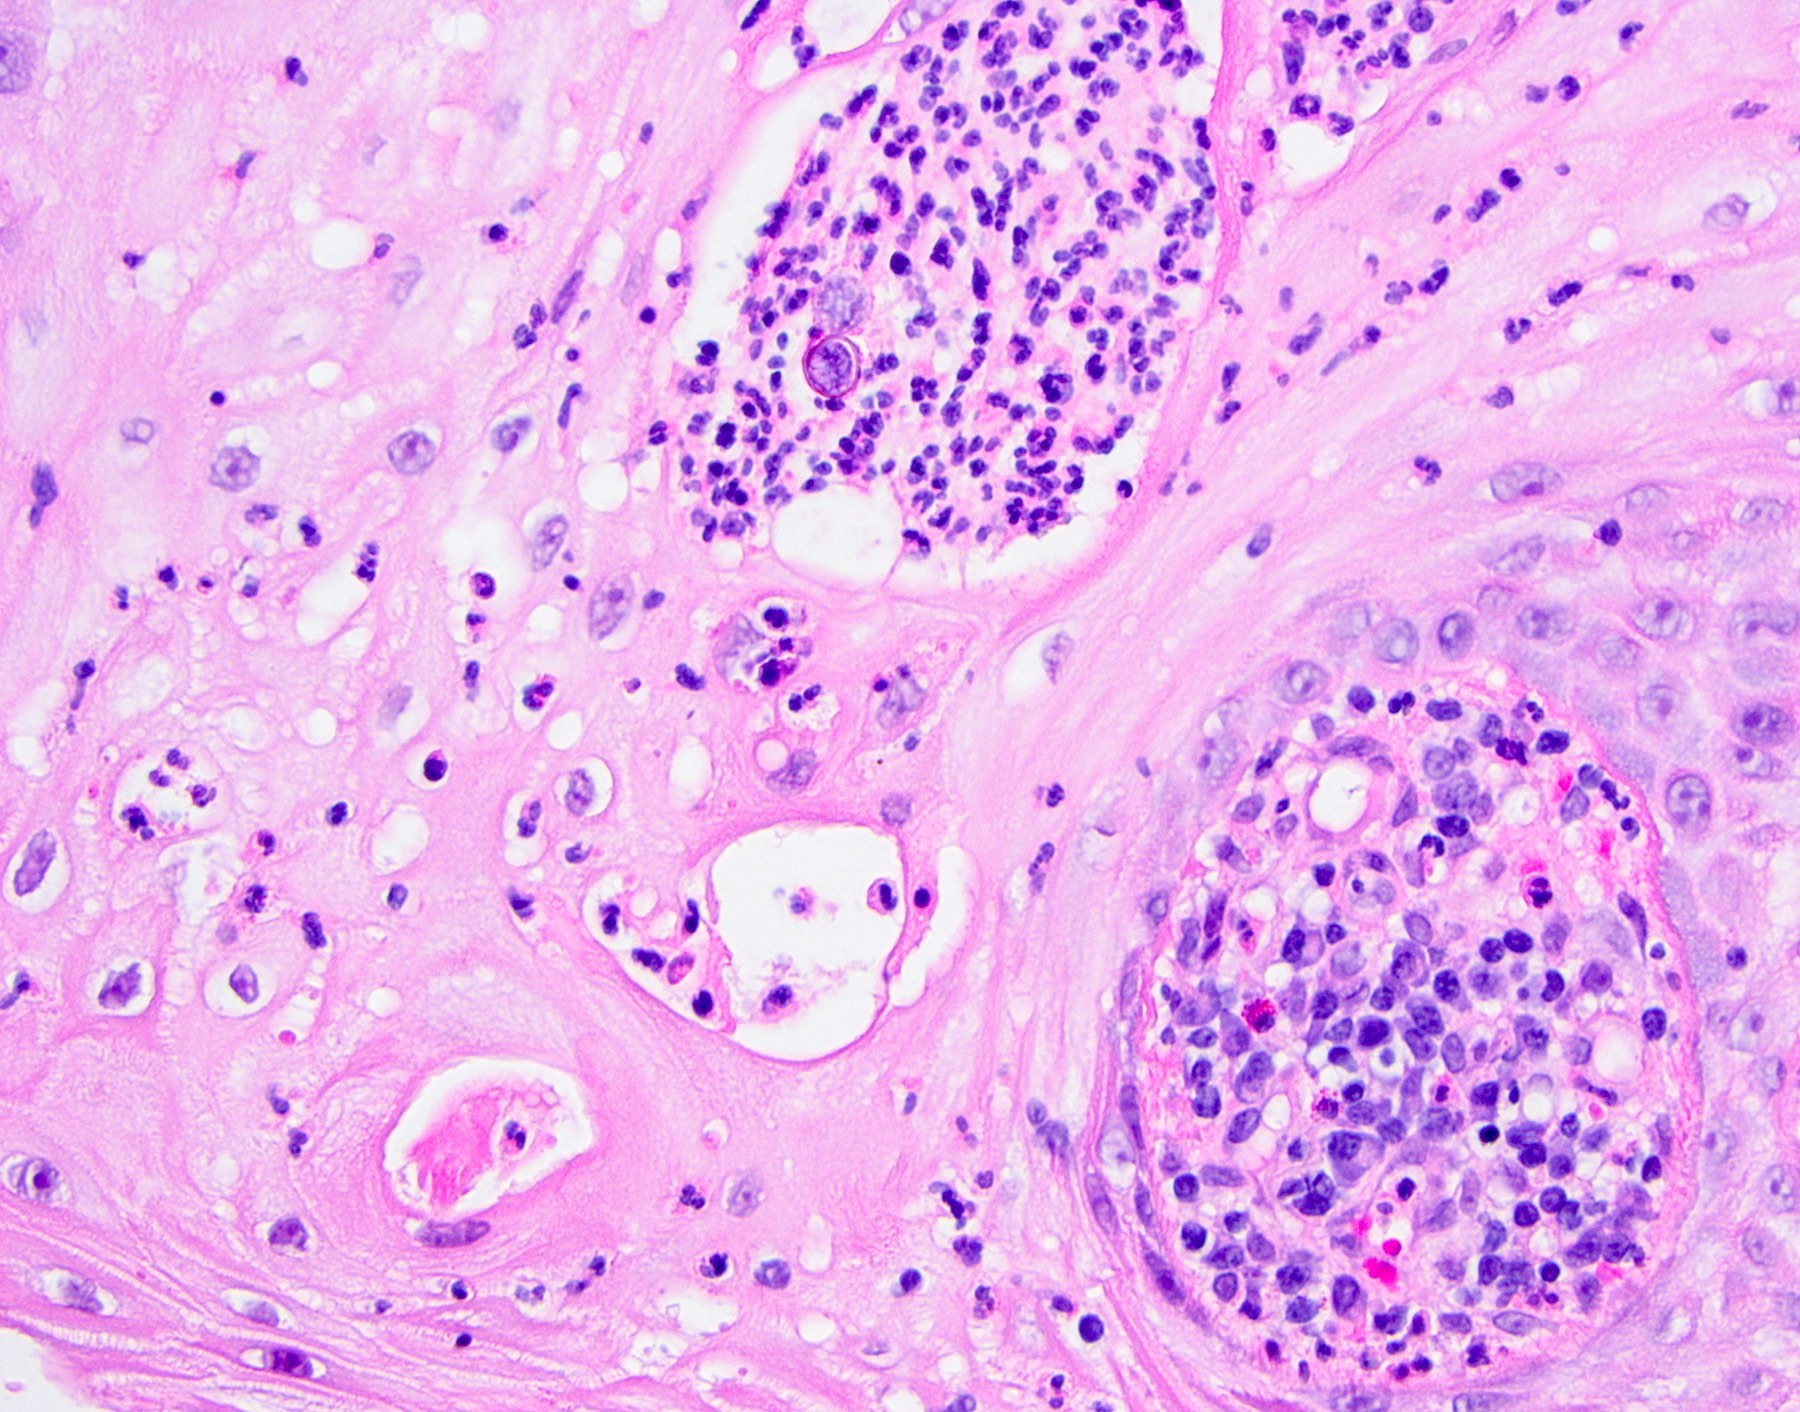

Microscopic (histologic) description

• Thick elongation of the overlying epithelium with bulbous or sometimes jagged / sharp, interconnecting rete ridges (Am J Dermatopathol 2011;33:112)

• May exhibit keratin pearl formation: concentric layers of keratinocytes with central keratinization (Am J Dermatopathol 2011;33:112)

• Lacks significant nuclear atypia; although mitotic figures may be seen, they are not numerous or atypical (Am J Dermatopathol 2011;33:112)

• Replacement of underlying fibrous stroma with sheets of pale, basophilic, plump granular cells suggests that the overlying epithelial proliferation is likely associated with granular cell tumor

Practice question #2

A patient presents with a yellow nodule on the tongue. What is the diagnosis?

1. Frictional keratosis

2. Granular cell tumor with overlying pseudoepitheliomatous hyperplasia

3. Squamous cell carcinoma

4. Verrucous carcinoma

Practice answer #2

B. Granular cell tumor with overlying pseudoepitheliomatous hyperplasia (PEH). Microscopic sections show a dome shaped mass of pale, basophilic, plump granular cells surfaced by hyperkeratotic and hyperplastic epithelium. Although the rete ridges are significantly proliferative and demonstrate keratin pearls, overt cytologic atypia is not appreciated. This proliferative pattern of the epithelium is termed pseudoepitheliomatous hyperplasia and is known to be associated with granular cell tumors. Answer A is incorrect because although there is a thickened layer of parakeratin, this answer choice ignores the replacement of the fibrous stroma by plump granular cells. Answer C, a common pitfall in the diagnosis of this tumor, is incorrect because although the epithelium is proliferative, prominent cytologic atypia is not appreciated. The pathologist must be keen in recognizing the underlying replacement of the fibrous stroma with plump granular cells and must know that granular cell tumors characteristically show PEH in many cases. Answer D is incorrect because verrucous carcinoma would show keratin clefting and prominent, bulbous, plunging rete ridges that push into the underlying muscle.